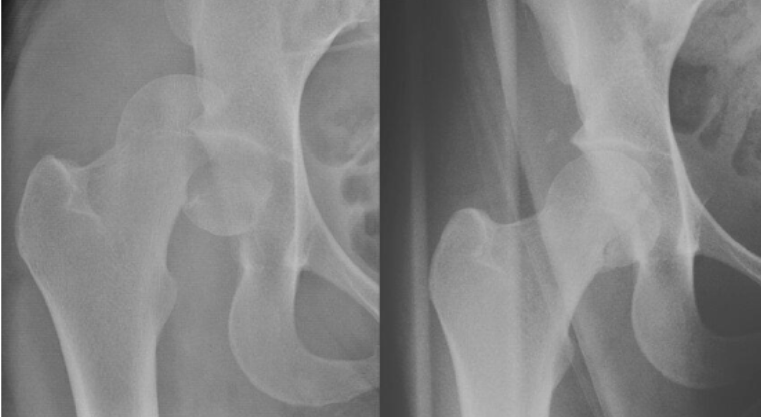

Fractura presente en esta radiografia

Intertrocanterica

Mecanismo de lesion de esta fractura

Jovenes: Alta energia

Ancianos: Caisa simple, impacto directo en trocanter mayor

De acuerdo a la clasificacion de EVANS esta fractura se considera

Inestable

Estable

Tratamiento de fractura intertrocanterica

Idealmente <48hrs post lesion

Clavo endomedular con tornillo deslizante

Tratamiento de fractura intertrocanterica en pacientes con comorbilidades graves

Protesis parcial (De Thompson)